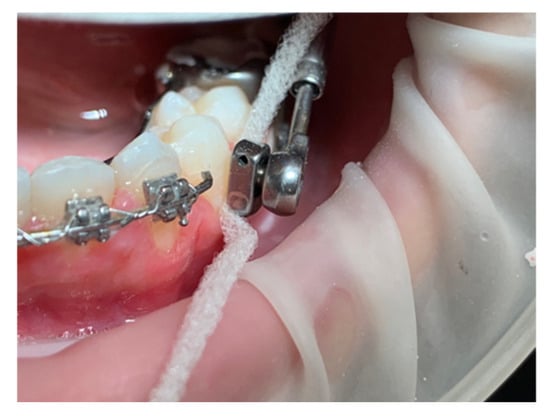

Figure 6.

The super floss does not easily slice thanks to the space between the metal and the tooth surface.

In the lower arch, only the first molars suffer the mesializing forces instead of the four teeth per arch in the original device design. The spatial instability of the metal elements can also occur on the lower arm welded to the band of the lower molar. The muscular force may determine the creation of a lever arm, which discharges its force on the lower molars; possible slight displacements of the terminal part of the arm could create a direct mucosal decubitus or an unwanted vestibularization of the first premolar, which cannot be controlled by wire sectionals. The reduced space between the arm and the dental surfaces of the premolars allows the rectangular wire section used in the anterior sector from canine to canine to reduce the displacement of the dental elements. Therefore, the lower premolars remain without any movement control. The premolars may vestibularize and come into contact with the appliance. Therefore, we recommend increasing the space between the welded arm and the teeth. Moreover, the patient will be able to monitor the status of the device during daily home oral hygiene procedures. In fact, the area can be cleaned with a specific type of dental floss.